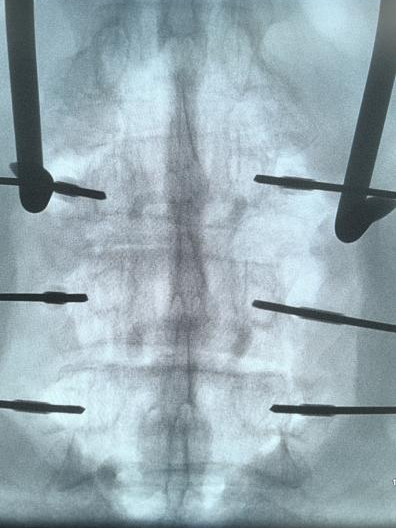

▲术中椎弓根螺钉精准置入

术后复查X线、CT